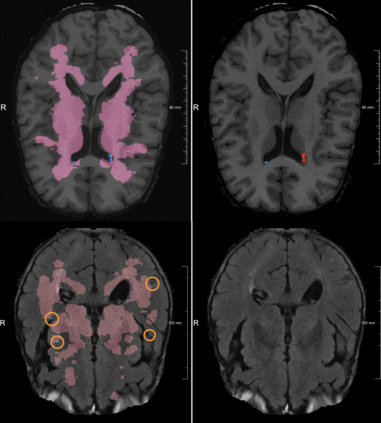

Lacunes of presumed vascular origin are fluid-filled cavities of between 3 - 15 mm in diameter, visible on T1 and FLAIR brain MRI. Quantification of lacunes relies on manual annotation or semi-automatic / interactive approaches; and almost no automatic methods exist for this task. In this work, we present a two-stage approach to segment lacunes of presumed vascular origin: (1) detection with Mask R-CNN followed by (2) segmentation with a U-Net CNN. Data originates from Task 3 of the "Where is VALDO?" challenge and consists of 40 training subjects. We report the mean DICE on the training set of 0.83 and on the validation set of 0.84. Source code is available at: https://github.com/hjkuijf/MixLacune . The docker container hjkuijf/mixlacune can be pulled from https://hub.docker.com/r/hjkuijf/mixlacune .